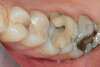

SECTEURS POSTÉRIEURS MAXILLAIRES ET MANDIBULAIRES

Remplacement de composites et/ou d'amalgames (plombages) défectueux par une résine composite esthétique restaurant la morphologie initiale des dents.